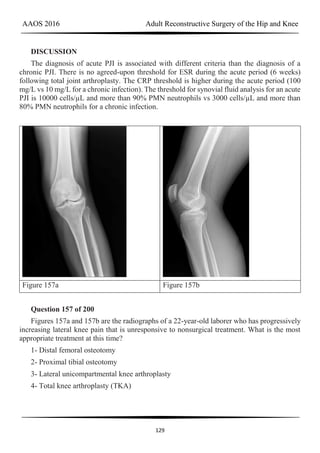

periprosthetic fracture is 11%, according to Chevillotte and associates. Obtaining presurgical

aspiration or tissue for culture intrasurgically is recommended if concomitant infection is

suspected.

Figure 101a Figure 101b Figure 103a

AAOS 2016 Adult Reconstructive Surgery of the Hip and Knee

83

Figure 103b Figure 103c Figure 103d

CLINICAL SITUATION FOR QUESTIONS 101 THROUGH 104

Figures 101a and 101b are the right hip radiographs of a 26-year-old active man who has

had pain in his right hip for 4 months. His pain is worse with prolonged periods in a seated

position. He has no pain at rest and denies pain in other joints or systemic illness. Examination

reveals passive range of motion of full extension, 80 degrees of flexion, internal rotation in

flexion of 0 degrees, and external rotation in flexion of 30 degrees. Forced flexion, internal

rotation, and adduction are very painful. A flexion, abduction, and external rotation test result

is negative.

Question 101 of 200

What is the most common morphologic abnormality among patients with this condition?

1- Pathologic femoral morphology

2- Pathologic acetabular morphology

3- Femoral neck retroversion

4- Combined pathologic femoral and acetabular morphology

PREFERRED RESPONSE: 4- Combined pathologic femoral and acetabular morphology